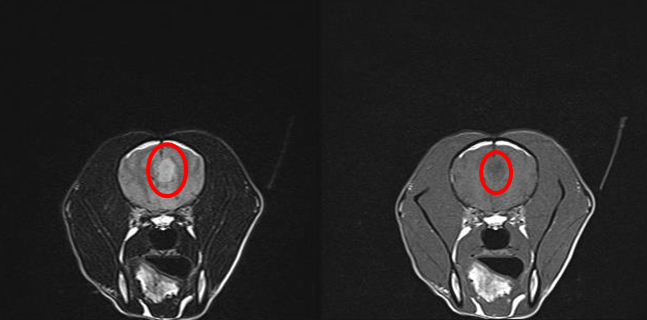

患者の頭部MRI撮影像(FLAIR像) 患者の頭部MRI撮影像(T1強調像)

左図:横断面、右図:横断面